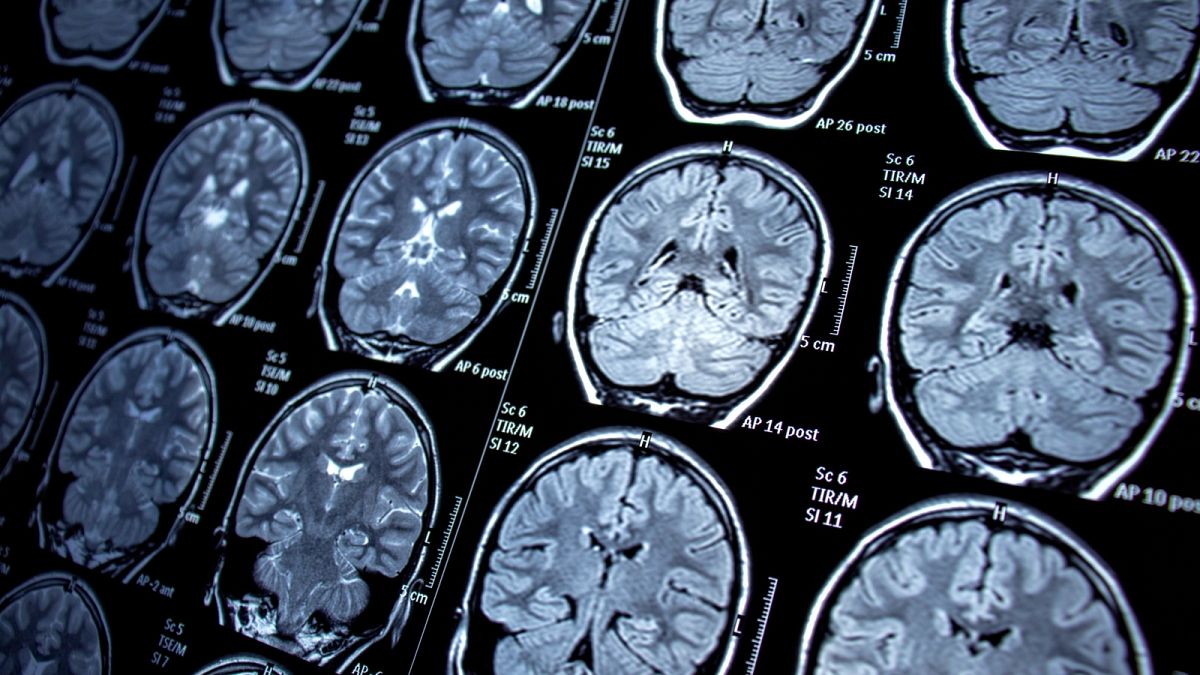

Contrairement à la plupart des scanners, l’imagerie par résonance magnétique utilise des champs magnétiques pour produire des images détaillées des structures à l’intérieur du corps plutôt que des radiations.

L’IRM signifie imagerie par résonance magnétique. Il s’agit d’un type d’examen médical qui utilise des champs magnétiques pour produire des images détaillées des organes, des os et d’autres structures à l’intérieur du corps. Contrairement à de nombreux autres types d’examens, l’IRM n’utilise pas de rayonnement.

Les médecins demandent une IRM pour diagnostiquer un cancer, des lésions cérébrales, des vaisseaux sanguins endommagés et d’autres problèmes médicaux. Les scanners du corps entier peuvent prendre une heure ou plus, les patients étant allongés immobiles dans un tube cylindrique.